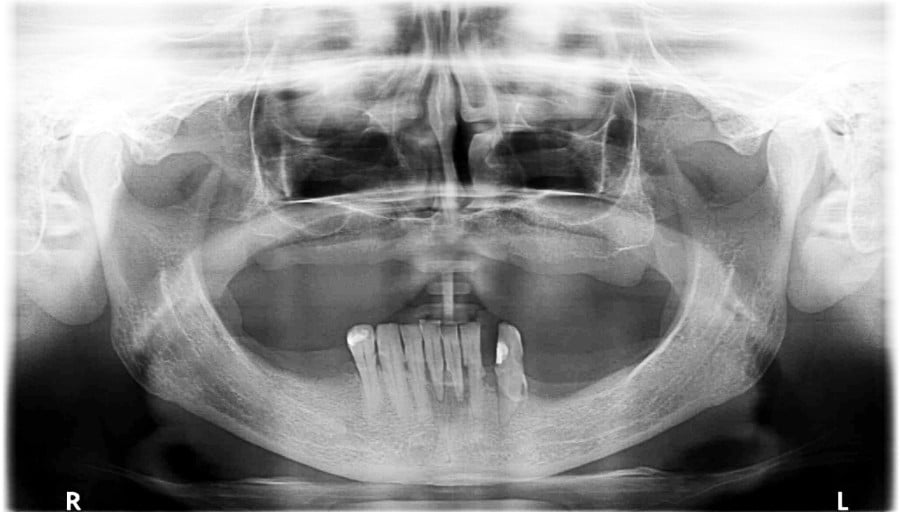

Pacjentka lat 65, zgłosiła się do stomatologa na konsultację, ponieważ niepokoiła ją ruchomości zębów. W pierwszej kolejności została skierowana na wizyt higienizacyjną. Bezzębie w łuku górnym zaopatrzone było całkowitą akrylową protezą, w łuku dolnym pacjentka nie użytkowała żadnego uzupełnienia. Pacjentka niepaląca.

Postępowanie rozdzielono na dwie wizyty. Badaniem klinicznym, oceniając wskaźniki periodontologiczne, uzyskano wartości API 100%, PBI 100% świadczące o konieczności poprawy higieny i procesie zapalnym dziąseł, duże złogi kamienia nad i poddziąsłowego, bardzo obfity biofilm, pogłębione wszystkie kieszonki dziąsłowe, ciężkie zapalenie dziąseł, ruchomości zębów dolnych III stopnia, duży zanik kości. Badanie kliniczne błony śluzowej jamy ustnej nie wykazało zmian patologicznych.